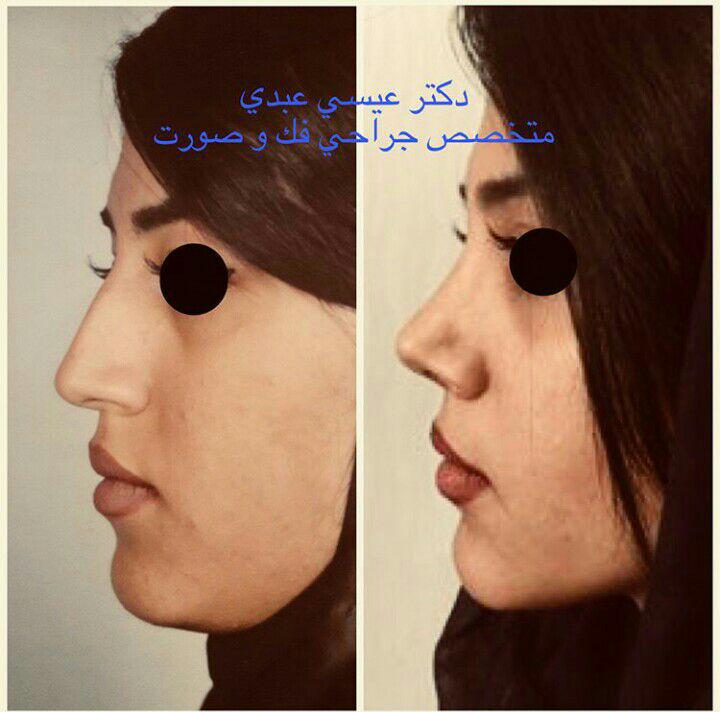

دکتر عیسی عبدی در رشت

– متخصص جراحی فک , پلاستیک صورت و بینی

جراحی فک , پلاستیک , صورت وبینی

جراحی ترمیمی و زیبایی فک و صورت و جمجمه و گردن